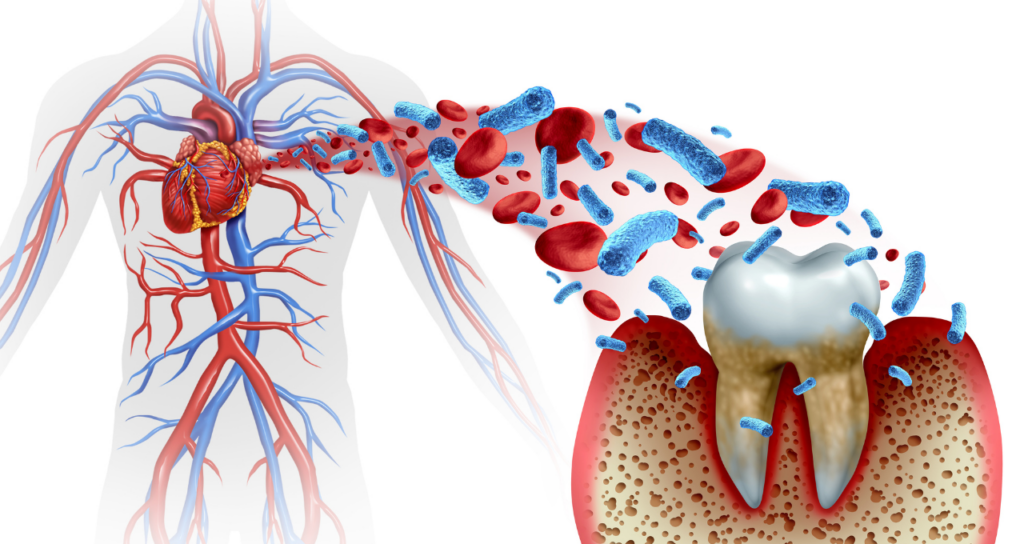

成人の約8割が罹患しているとも言われるこの病気は単に、お口の中だけの問題ではありません。

しかし、それ以上に恐ろしいのは歯周病菌やその毒素が血管を通じて全身に巡り、糖尿病や心筋梗塞、脳梗塞といった命に関わる疾患を引き起こす引き金になるという事実です。

糖尿病と歯周病は互いに悪影響を及ぼし合う、「相互関係」にあります。

糖尿病の方は免疫力が低下しているため歯周病にかかりやすく、かつ重症化しやすい傾向があります。

一方で歯周病による炎症性物質が血液中に入り込むと、インスリンの働きを妨げ血糖コントロールを悪化させることが分かっています。

循環器疾患へのリスク管理

歯周病菌が血流に乗って心臓に到達すると血管の動脈硬化を促進させたり、心内膜炎を引き起こしたりするリスクが高まります。